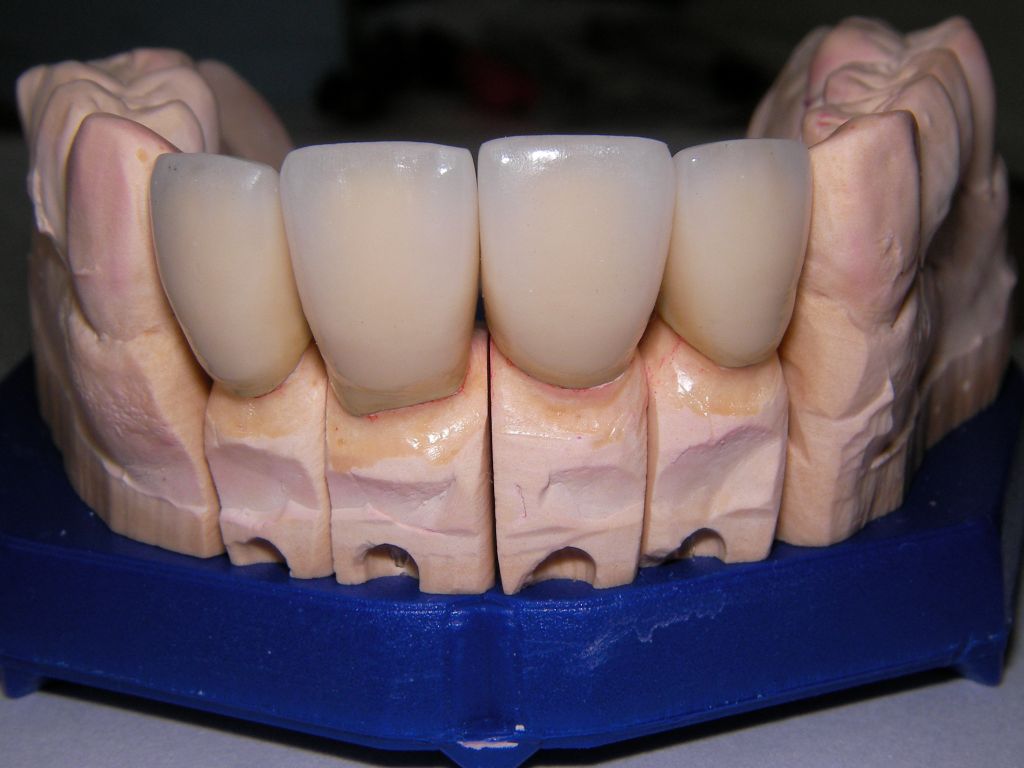

Am 28.2.06 erfolgte die endgültige Präparation (das "Beschleifen") aller 4 Zähne. Links das Modell, auf dem die Kronen gefertigt worden waren. Rechts kurz vorm Zementieren der Kronen am 13.3.06. Aus der Längendifferenz der Zähne rechts und links kann man darauf schließen, daß die Präparation tief unter dem Zahnfleisch erfolgen mußte. |

Links die Kronen aus dem Dentallabor "Heitmeyer Zahntechnik", Osnabrück. Man sieht praktisch keinen Metallrand. Der Patient war zur Farbbestimmung im Dentallabor - so halten wir es praktisch immer. Rechts das Ergebnis bei der 1. Nachkontrolle am 27.3.05. Das Zahnfleisch muß sich noch etwas erholen. |